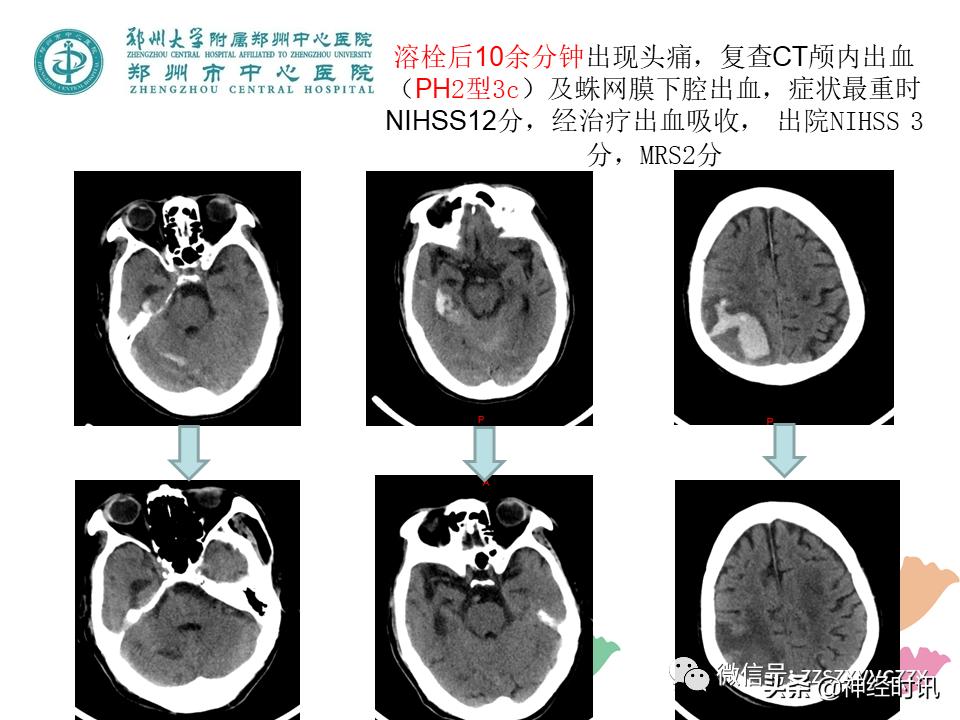

1.HT的发生率跨度非常大,与溶栓药物的剂量选择、溶栓时间窗、评价标准有直接联系。

2.HT有证据的危险因素有:卒中严重程度、高龄、肥胖、高血压、房颤、糖尿病、基线血糖水平高、基线中性粒细胞计数升高、低游离L3水平、肾功能不全、心衰、缺血性心脏病、抗血小板药物使用、CT上显示大范围明显低密度者、严重的白质疏松、高负荷脑微出血(大于10个微出血灶)。ASPECTS评分<7分的患者通常病情重,静脉溶栓后更易发生出血转化;